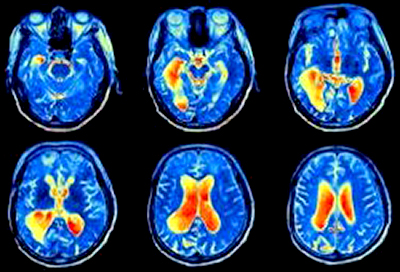

Um estudo recente revelou a idade exata em que o cérebro inicia um processo acelerado de envelhecimento |

Os cientistas chamam esse período de “janela crítica”, quando o cérebro começa a ter menor acesso à energia antes que ocorra um dano irreversível. Para chegar a essa conclusão, a equipe analisou exames de ressonância magnética funcional (fMRI) de mais de 19 mil pessoas, mapeando a atividade cerebral e identificando áreas em declínio.

Ressonância magnética funcional do cérebro. (Reprodução/iclnoticias.com.br/) |